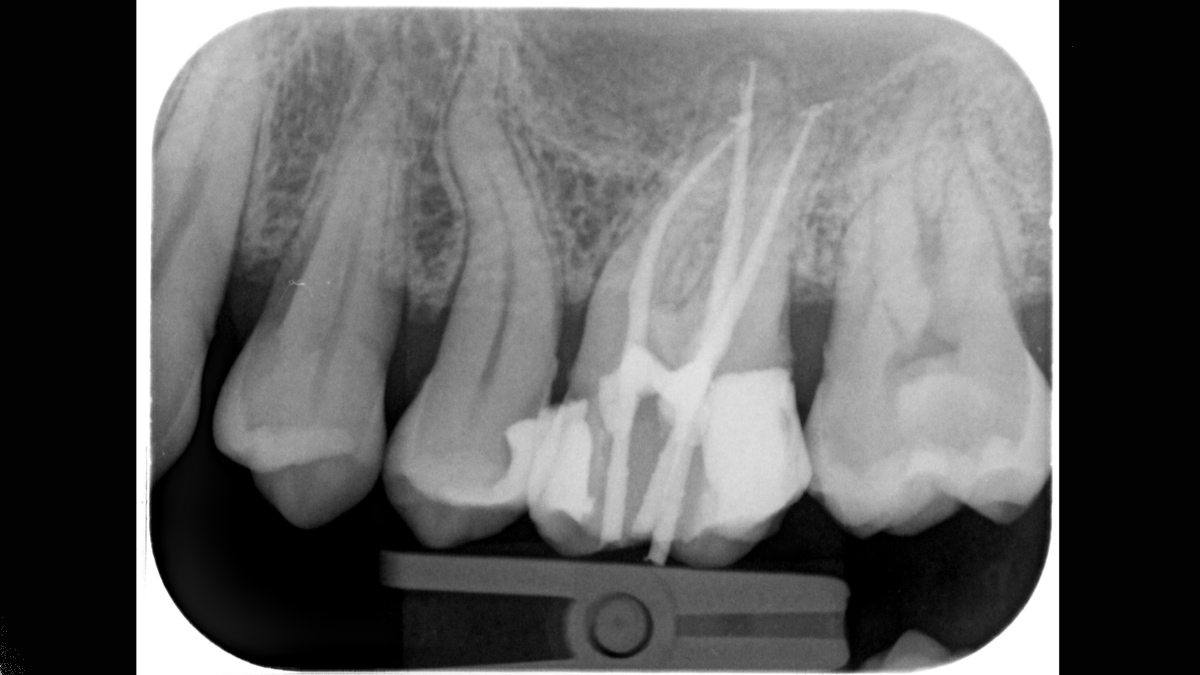

- Kiemelkedő képminőség a hatékony diagnózis érdekében

A Xios Scan speciálisan a szkennerhez tervezett lemezekkel működik, 22 lp/mm felbontással. - Karcmentes letapogatás a reprodukálható képminőség érdekében

A Xios Scan legfeljebb 22 lp/mm elméleti felbontásban működik. Az eredmény rendkívül éles és részletgazdag képek – a pontos diagnózis ideális feltételei. A képeket közvetlenül a Sidexis 4 szoftverhez továbbítják, ahol lehetőség van tovább értékelni és diagnosztizálni. A szoftver egyszerű vezérlésével a röntgen későbbi szerkesztéshez (élesség, fényerő, kontraszt) egyszerűen megjeleníthető.